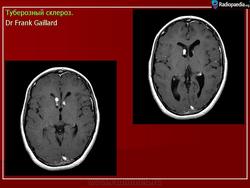

Туберозный склероз, или синдром Бурневиля - Прингля.

Туберозный склероз (болезнь Бурневилля-Прингла, синдром Бурневилля - Брессау) - глиоз белого вещества мозга, проявляющийся в раннем детстве эпилептическими припадками (в 85%), олигофренией в сочетании с нараста­ющей пирамидной и экстрапирамидной симптоматикой, кожной патологией. В возрасте 4-6 лет на лице в форме бабочки в области носа обычно появляют­ся множественные желто-розовые или коричнево-красные узелки диаметром чуть больше 1 мм - аденомы Прингла, которые обычно признаются аденомами сальных желез, однако есть мнение и о том, что они представляют собой про­исходящую из нервных элементов кожи гамартрому.

На поверхности мозга наблюдаются единичные или множественные глиома-тозные узлы, по цвету несколько светлее окружающего мозга и плотнее его на ошупь, возможна их кальцификация. Узлы могут быть и в белом веществе, под­корковых ганглиях, а также в стволе мозга и в мозжечке.

Встречаются и аномалии развития извилин мозга в виде микро- и пахигирии. Заболевание чаще носит спорадический характер. Бляшки достигают диаметра 5-20 мм. В коре больших полушарий и мозжечка иногда могут быть обнару­жены пластинчатые тельца, напоминающие амилоид. Происходит дегенерация клеток коры. При КТ-исследовании головы нередко можно выявить кальцифика-ты и глиальные узелки в паравентрикулярной области, субэпендимарно вдоль на­ружных стенок боковых желудочков, в зоне межжелудочкового отверстия Мон­ро, реже - в мозговой паренхиме. На М РТ головного мозга в 60% выявляются гипотеденсивные очаги в одной или обеих затылочных долях, которые расце­ниваются как участки неправильной миелинизации (Козлов А.В., 2002).